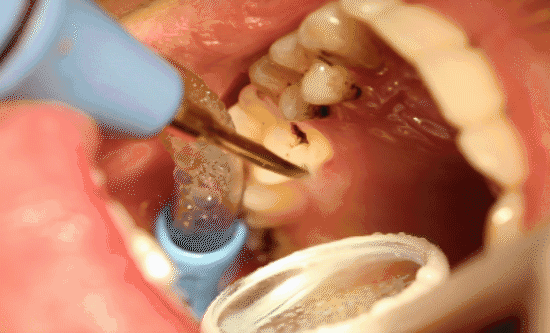

1、洗牙会导致牙缝变大吗?

不会。当你觉得洗牙后牙缝变大了,那是由于牙龈萎缩,牙根外漏,牙缝已经存在,牙缝平时有牙石覆盖,感觉不到,洗牙后,牙面以及牙齿间隙中的污物被清除,才会让牙缝感觉变大了。如果牙石不及时清除,牙龈会进一步萎缩,牙缝会更大。